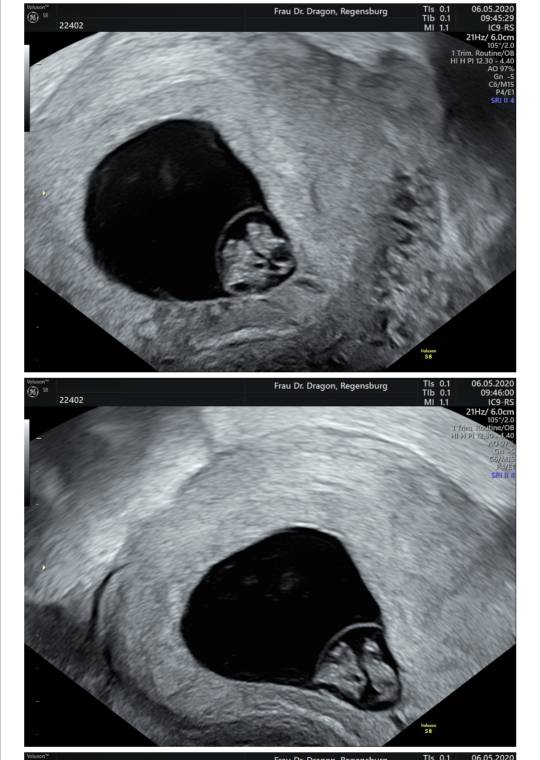

Jest serducho [emoji3590] waliło jak oszalałe - mały człowiek we mnie mieszka [emoji7]

Słabo go trochę widać na zdjęciu przez moją tkankę tłuszczową hehe... trudno, najwyżej nie bedzie miec ladnych zdjęć w brzuchu póki co [emoji13]

Termin z USG na 31.12 - 01.01. [emoji3059] Będzie impreza [emoji4]

Za nic nie pamiętam ile ma długości...8,4 mm? Już nie słuchałam taka byłam zakręcona.